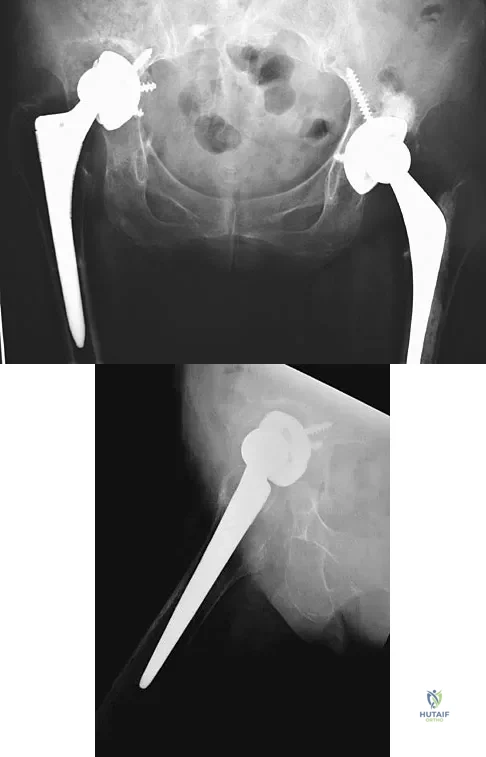

A 32-year-old man has posttraumatic arthritis after undergoing open reduction and internal fixation of a left acetabular fracture. A total hip arthroplasty is performed, and the radiograph is shown in Figure 18. What is the most common mode of failure leading to revision in this group of patients?